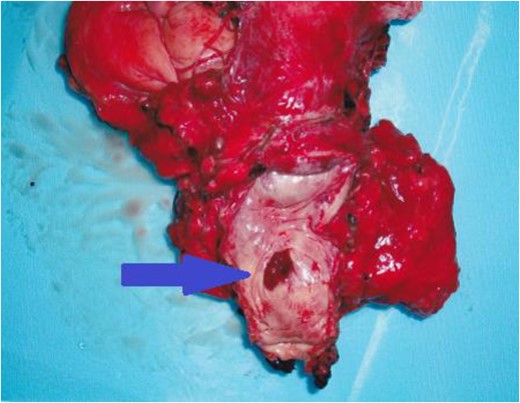

On admission, we performed standard open total cystectomy with lymph node excision and ileal conduit. The resected specimen showed the mass on the anterior vaginal wall (Fig. 2). Histopathological examination of the specimen showed adenocarcinoma tumor that continues to anterior vaginal wall, but urethral diverticular wall could not be identified (Fig. 3). We could not establish a diagnosis of urethral diverticulum; however, we clinically diagnosed as urethral diverticular adenocarcinoma. The proximal margin was negative, and all lymph nodes were negative. Because the post-surgical course was uneventful, the patient was discharged from our hospital on Day 27 post-surgery. The patient is doing well without recurrence or metastasis for 12 months.

Histopathological examination of the specimen showed adenocarcinoma tumor which continues to anterior vaginal wall, but urethral diverticular wall could not be identified.